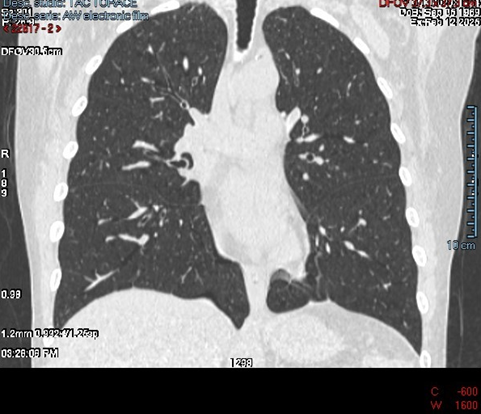

The patient experienced eventual wound healing and stabilisation of her reconstructive course following autologous flap reconstruction. However, she developed significant pulmonary sequelae manifesting as bullous lung disease and reduced pulmonary volume as the CT scan images of the lung clearly show with pulmonary emphysema with some millimetre-sized blebs and pulmonary cyst (Figure 1, 2). These changes resulted in chronic breathlessness, reduced capacity for physical activity, and long-term impairment in quality of life. On the walking test and pulmonary function test the patient showed a reduction of the value of the range expected for her age, height and sex.

Figure 1: CT Scan of the lungs of the Patient: coronal view. There is a pulmonary emphysema with some millimeter-sized blebs and pulmonary cyst. This finding was absent in June 2016 before the first surgical intervention.